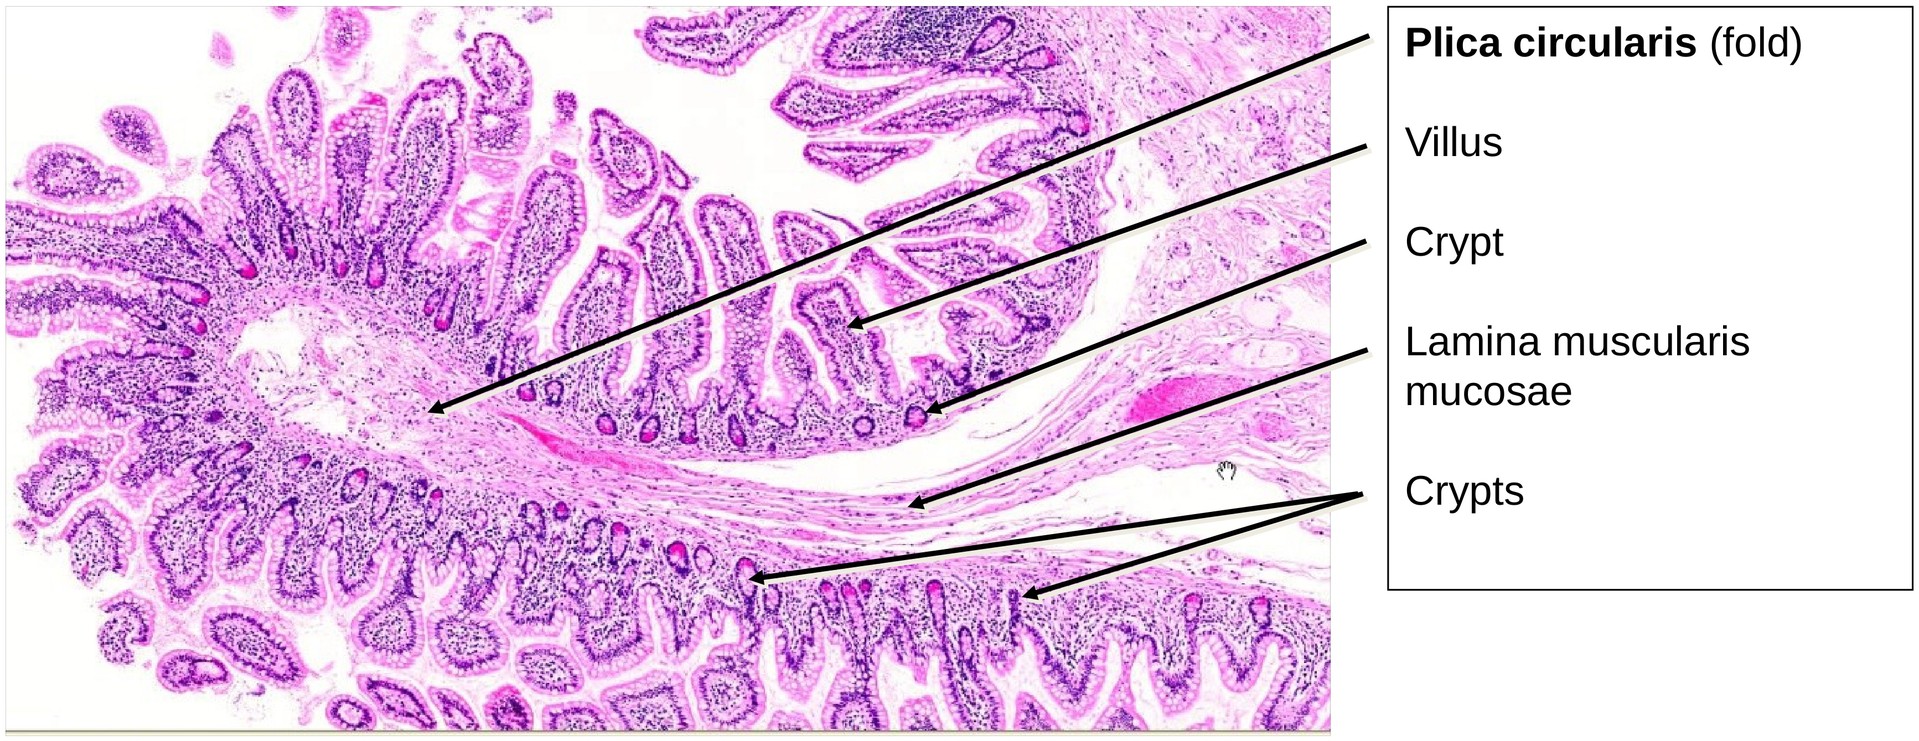

The general layered organization of the GIT wall is well preserved: - Tunica mucosa (with lamina epithelialis, lamina propria, and lamina muscularis mucosae). - The muscularis mucosae is relatively thin but extends into the circular folds and occasionally into the villi. - Tela submucosa, which appears robust but shows few identifiable elements of the submucosal plexus (Meissner’s plexus). - Tunica muscularis, composed of: - An inner circular layer (particularly prominent here). - An outer longitudinal layer, between which the myenteric plexus (Auerbach’s plexus) is clearly visible, containing ganglion cells and nerve fibers.

The circular folds (plicae circulares) are lower than those seen in the duodenum or jejunum. No glands are found in the submucosa (unlike Brunner’s glands in the duodenum).

The epithelium of the villi shows numerous goblet cells, interspersed among the enterocytes bearing a distinct brush border. Between the villi, short intestinal crypts (crypts of Lieberkühn) extend into the lamina propria.